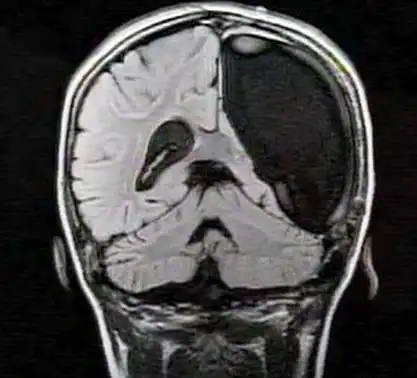

6. Идеальное зрение только одним полушарием

Совершенное зрение 10-летней немецкой девочки поставило в тупик врачей, поскольку она родилась только с левым полушарием головного мозга. Для хорошего зрения необходимо наличие обоих полушарий, потому что визуальная информация, поступающая от зрительных нервов, передается в противоположное полушарие для переработки и хранения там. Так, наличие лишь одного полушария должно свидетельствовать о том, что должен работать лишь один глаз, в случае с девочкой, только правый.

Тем не менее, девочка отлично видит, и наслаждается нормальным, бинокулярным зрением, а в 2010 году врачи отсканировали ее мозг, чтобы понять причину происходящего. Оказалось, что посредством процесса, известного, как пластичность, зрительный нерв из левого глаза мигрировал в ее левое полушарие, другими словами, левая часть мозга девочки принимает визуальную информацию от обоих глаз.

Поразительно, в зрительной коре ее левого полушария сформировались специальные районы, предназначенные для обработки информации, получаемой левым глазом. Это помогает избежать путаницы.